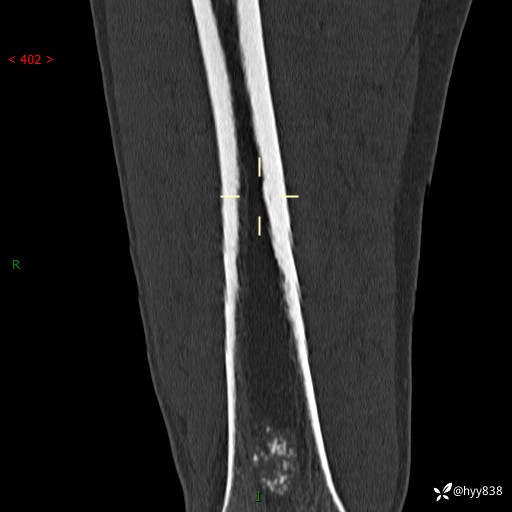

CT

img